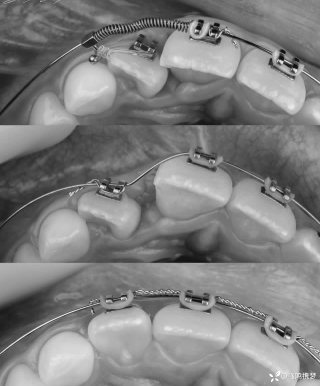

烧伤整形邹普功烧伤科医师

活动背景和目的:我从去年九月份陆续在丁香园写了几十帖有关腋臭微创手术的帖子,受到很多同行老师的关注及跟帖,其中有很多同行老师也在尝试用我的这种方法治疗狐臭,并且收到很好的效果。随着站内外科同行对狐臭微创手术的关注度日渐增高,近期受丁香园邀请,特举办一次关于狐臭微创手术的跟学练活动。这也是本人根据临床工作中的一些手术案例总结的经验,分享给大家一起交流学习。让我们一起做好除臭这件事!各位站友可点击下面狐臭专场链接交流学习(包含本人视频操作教学详解、常见问题讨论和各位站友同行的手术佳作):https://3g.dxy.cn/newh5/view/nodeActivityTopic/270第一期我给大